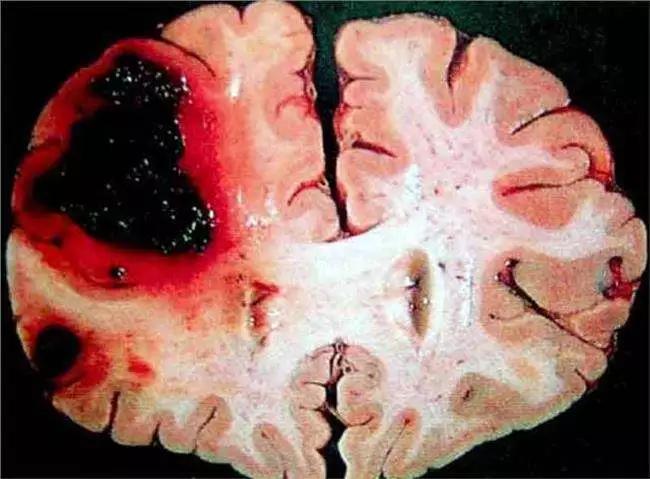

腦出血是指非外傷性腦實質內血管破裂引起的出血,占全部腦卒中的20%~30%,急性期病死率為30%~40%。發(fā)生的原因主要與腦血管的病變有關,即與高血脂、糖尿病、高血壓、血管的老化、吸煙等密切相關。那么腦出血是怎么引起的呢?

腦出血是常見的腦血管疾病之一,是多種原因引起腦部血管破裂出血,導致腦組織缺血發(fā)生功能障礙。出現(xiàn)頭暈、頭痛、面部歪斜、言語不清偏癱、意識障礙等表現(xiàn)。原因包括: